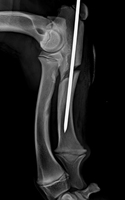

Oberarmfraktur |